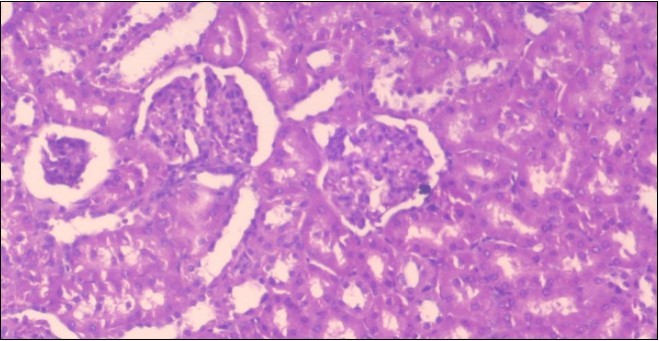

The histological examination of the kidney of the control rats fed on a standard diet showing normal rounded capsules with normal Bowman's glomeruli, round proximal tubules and elongated distal tubules with high cuboidal cells figure 1. The rats fed (HFD) showed fatty degeneration of the tubules with eosinophilic material deposition, glomerular atrophy with wide urinary space and distal tubules with extrusion of nuclei into lumen figure 2. By comparison kidneys of rats which were treated by fennel after being obese and the control rats observed partial improvement in both Bowman's capsules and proximal tubules. Note the distal tubules show less focal fatty infiltration figure 3.While examination of rats kidney that were treated by ator after obesity showed improvement in Bowman's capsules with normal glomerular and partial improvement in proximal tubules and distal tubules, figure 4. Kidney of rats that were treated by fennel and ator after obesity and the control rats showed high improvement in the tissues with normal glomerular and that Most of Bowman's capsules and renal tubules, restoring their normal appearance figure 5.

Figure 2.Photomicrogragh of kidney section of obese rat showing fatty degeneration of the tubules with eosinophilic matrial deposition, glomrerular atrophy with wide urinary space and distal tubules with extrusion of nuclei into lumen , (H&E) (40X).